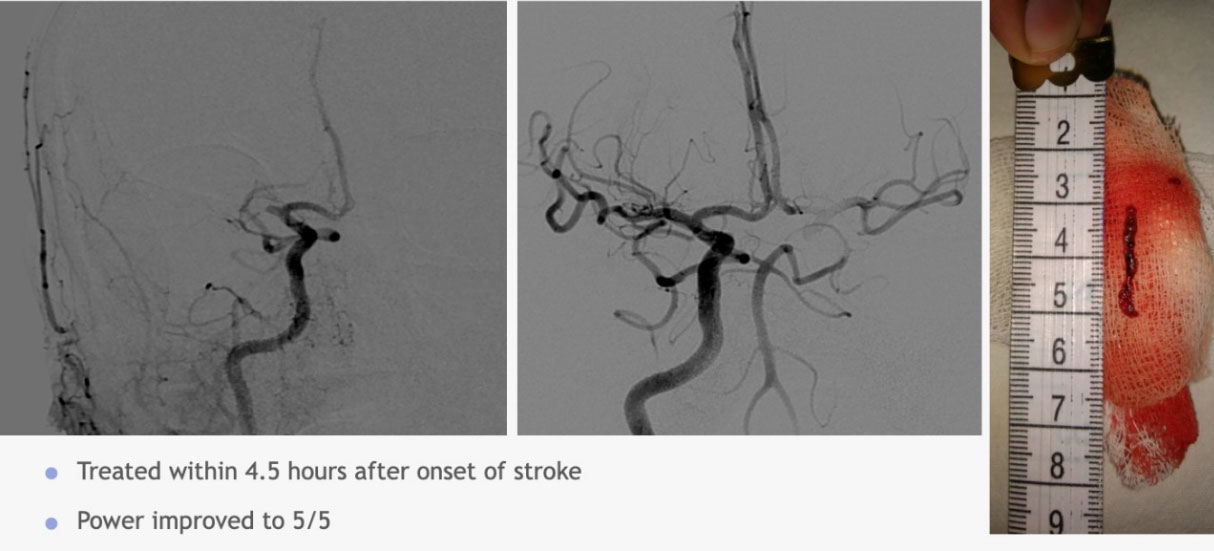

Mechanical thrombectomy

A procedure that can be done upto 6 hours of Stroke onset uses a tiny device to remove clot from an artery in the brain, restoring blood flow. This procedure is an option for some patients who cannot receive drug therapy or who have failed drug therapy.